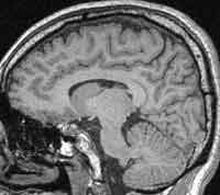

Alcuni scienziati americani hanno rivisto la tradizionale comprensione genetica della schizofrenia, mettendo alla luce nuove mutazioni coinvolte nella malattia. In un recente articolo pubblicato su Nature Genetics, un team del Columbia University Medical Center di New York ha individuato 40 nuove mutazioni presenti in almeno la meta’ dei casi di schizofrenia privi di storia familiare. Lo studio, secondo i ricercatori, potrebbe essere un risposta alla domanda sull’elevata incidenza di casi di schizofrenia nel mondo. La schizofrenia e’ una malattia piuttosto diffusa, colpendo una persona su 100. I geni sono senz’altro coinvolti, un decimo delle persone affette da schizofrenia hanno infatti un genitore con la malattia. Dallo studio emerge ora che anche nei casi in cui la malattia non e’ ereditata, i geni continuano a svolgere una funzione essenziale. E’ noto che il Dna di una persona non e’ una copia perfetta del codice genetico dei genitori. Il teamdella Columbia ha analizzato il codice genetico di 225 persone, alcune con la malattia altre senza, e dalle analisi sono emerse 40 nuove mutazioni legate alla schizofrenia. Xu Bin, responsabile della ricerca, ha dichiarato: "L’identificazione dei danni legati a queste mutazioni formatesi de novo, ha radicalmente trasformato la nostra comprensione delle basi genetiche della schizofrenia".

Maria Karayiorgou, un’altra ricercatrice coinvolta nel progetto, ha aggiunto: "Il fatto che le mutazioni provengano tutte da geni diversi e’ particolarmente affascinante. Cio’ suggerisce che, molto piu’ di quanto abbiamo sospettato sinora, le mutazioni possono contribuire alla schizofrenia e cio’ e’ probabilmente dovuto alla complessita’ dei circuiti neurali colpiti dalla malattia. Sono infatti moltissimi i geni necessari al loro sviluppo e al loro funzionamento".